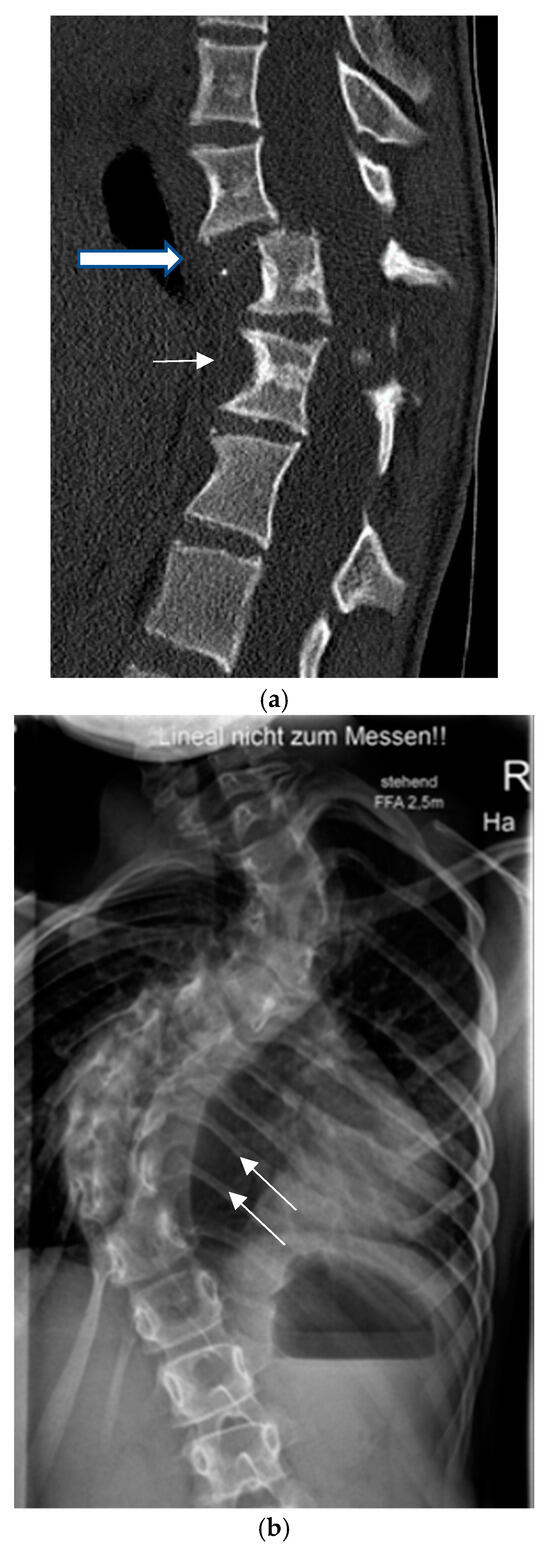

- Mladenov, K.V.; Spiro, A.S.; Krajewski, K.L.; Stücker, R.; Kunkel, P. Management of spinal deformities and tibial pseudarthrosis in children with neurofibromatosis type 1 (NF-1). Childs Nerv. Syst. 2020, 36, 2409–2425. [Google Scholar] [CrossRef]